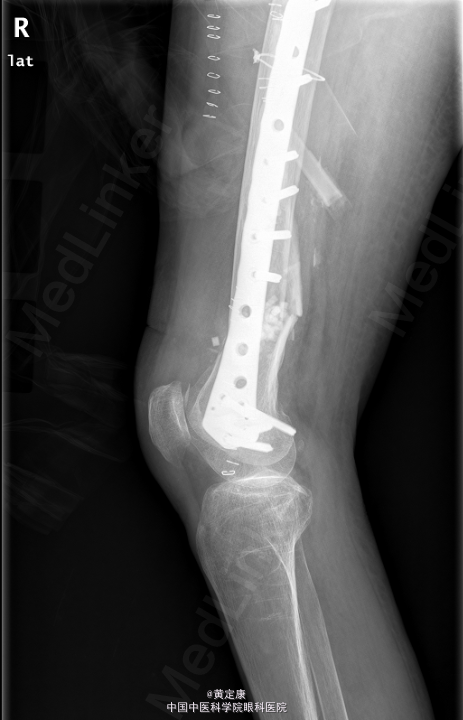

患者,女,82岁,因“摔伤致右下肢疼痛伴功能受限1天”入院。 患者1天前因外伤致右下肢剧烈疼痛,无法行走,。送至外院急诊,X线示“右股骨髁上骨折”,拟“右股骨髁上骨折”收治入院。

右膝部肿胀,膝关节活动受限,右足各趾活动感觉正常,末梢血运正常。石膏固定。检查提示:右股骨髁上骨折。

初步诊断: 右股骨髁上骨折 行[右]股骨骨折切开复位钢板内固定术